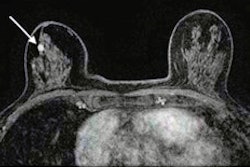

- Comparison of MRI and Ultrasound for Determining Abnormalities in Preterm Infants Medical Imaging helps in detecting and diagnosing diseases at its earliest and treatable stage and helps in determining most appropriate and effective care for the patient.”Medical imaging provides a picture of the inside of the […]

- Mammography vs. Ultrasound for Breast Tissue Analysis Mammography screening is one of the most recognized options for analyzing breast tissue in adult women. In contrast, the accuracy of this procedure allows it to be an alternative for women who cannot undergo mammography […]